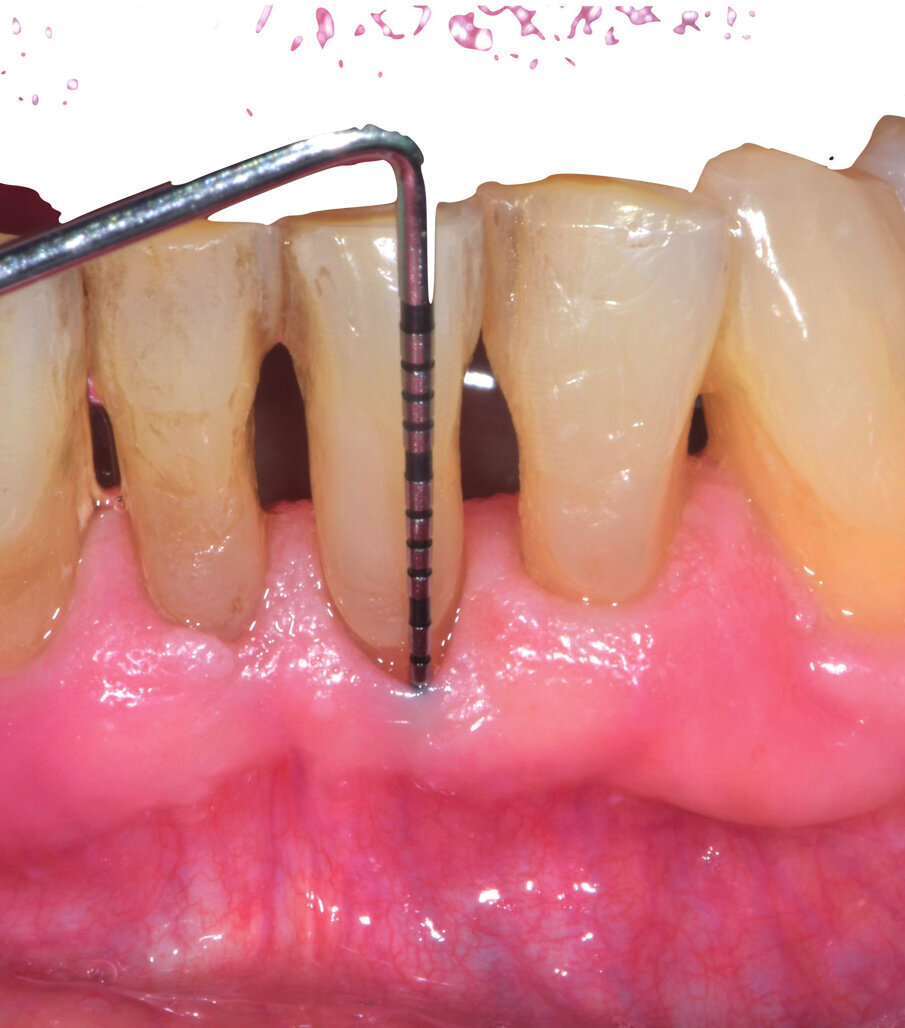

Il paziente di 71 anni con parodontite stadio III grado b presenta una tasca di 9 mm distale e vestibolare su 31 residua dopo trattamento causale (Figg. 6a, 6b). Il paziente presenta una buona igiene orale e aveva manifestato fastidio nella zona stessa. Le tasche presenti vengono ritrattate con u.s e curette mini-gracey e applicazione di Ozosan Gel per 8 min, lavaggio, nuova applicazione per 2 min e lavaggio con fisiologica (Fig. 7). A 3 settimane la zona si presenta con assenza di tasche patologiche (Fig. 8). Il paziente riferisce nessun disturbo in seguito al trattamento subito.

Figg. 6a, 6b - Sondaggio dopo terapia causale.